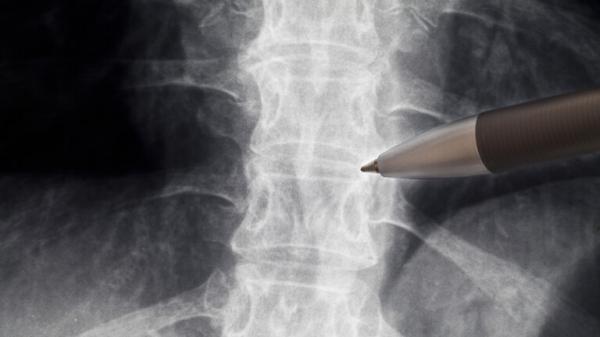

توصل العلماء إلى طريقة لإصلاح الألياف التالفة في العمود الفقري، التي لا تصلح نفسها بعد إصابة كبيرة، في خطوة كبيرة نحو عكس بعض أشكال الشلل وشفائها.

وقد تمكن فريق العلماء من إمبريال كوليدج لندن في إنجلترا من تحفيز تجديد الألياف المحورية في العمود الفقري للفئران بعد ثلاثة أشهر من تعرضها لإصابة مدمرة في العمود الفقري تركتها غير قادرة على المشي.

ورغم أن الفئران لم تستعد قدرتها على المشي، فهذه هي المرة الأولى التي يتمكن فيها الأطباء من إصلاح هذه الألياف في العمود الفقري، وفتح الباب أمام مزيد من البحث لإصلاح الضرر الناجم عن إصابة الحبل الشوكي (SCI).

وفي حين أن العلاج الطبيعي وأشكال العلاج الأخرى يمكن أن تساعد المصابين على استعادة بعض الوظائف ببطء، إلا أنه لا توجد طرق موثوقة لإصلاح العمود الفقري التالف وعلاج الشلل المرتبط بإصابات النخاع الشوكي.